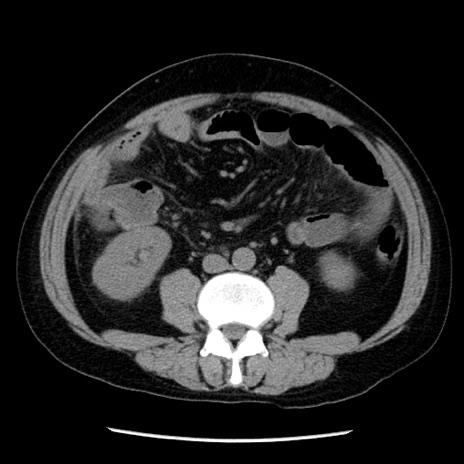

症例29(横断像)

【症例】40歳代男性

【現病歴】2日前から胃痛あり。徐々に周期的な激痛に変化した。本日になっても激痛があるため受診。

【身体所見】意識清明、BT 38-39℃台あり、腹部:膨満、やや硬、右下腹部に圧痛あり。

【データ】WBC 8500、CRP 23.26